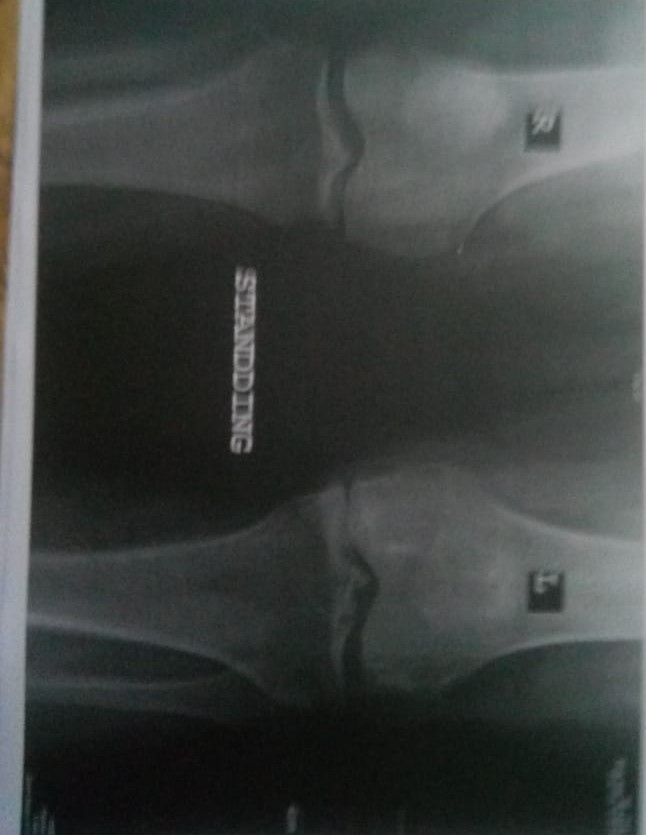

my mother is suffering from a lot of pain in her foot along with redness and swelling she did not had any injury or trauma to the foot. she went to an orthopedic who suggested the test for cbc , kindneys and crp iam attaching the results below . please kindly advice what could be wrong with her ,she has also started having some swelling in one hand now. she is also a patient of arthritis and blood pressure im attaching xrays and reports below

this could be a condition called pseudogout or gout. if she has fever then infection in the joints in an option. better to organize an appointment for further evaluation and management

anti ccp came 8 and Rh factor is negative please guide further

this is either cellulitis or gout. continue the medicine for 3 days. if not improved get a consultion